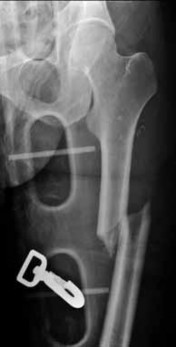

Question 1:

A 12-year-old obese male presents with left thigh pain and a limp. The provided radiograph is shown. He is diagnosed with a Slipped Capital Femoral Epiphysis (SCFE). What is the most widely accepted indication for prophylactic pinning of the contralateral hip?

Correct Answer: Age < 10 for girls or < 12 for boys, or underlying endocrinopathy

Explanation:

Prophylactic pinning of the contralateral hip is generally indicated in patients with metabolic or endocrine disorders (e.g., hypothyroidism, renal osteodystrophy) and in patients presenting at a very young age (girls <10, boys <12) due to a substantially increased risk of a contralateral slip. Recent literature also strongly weights the modified Oxford bone age score.